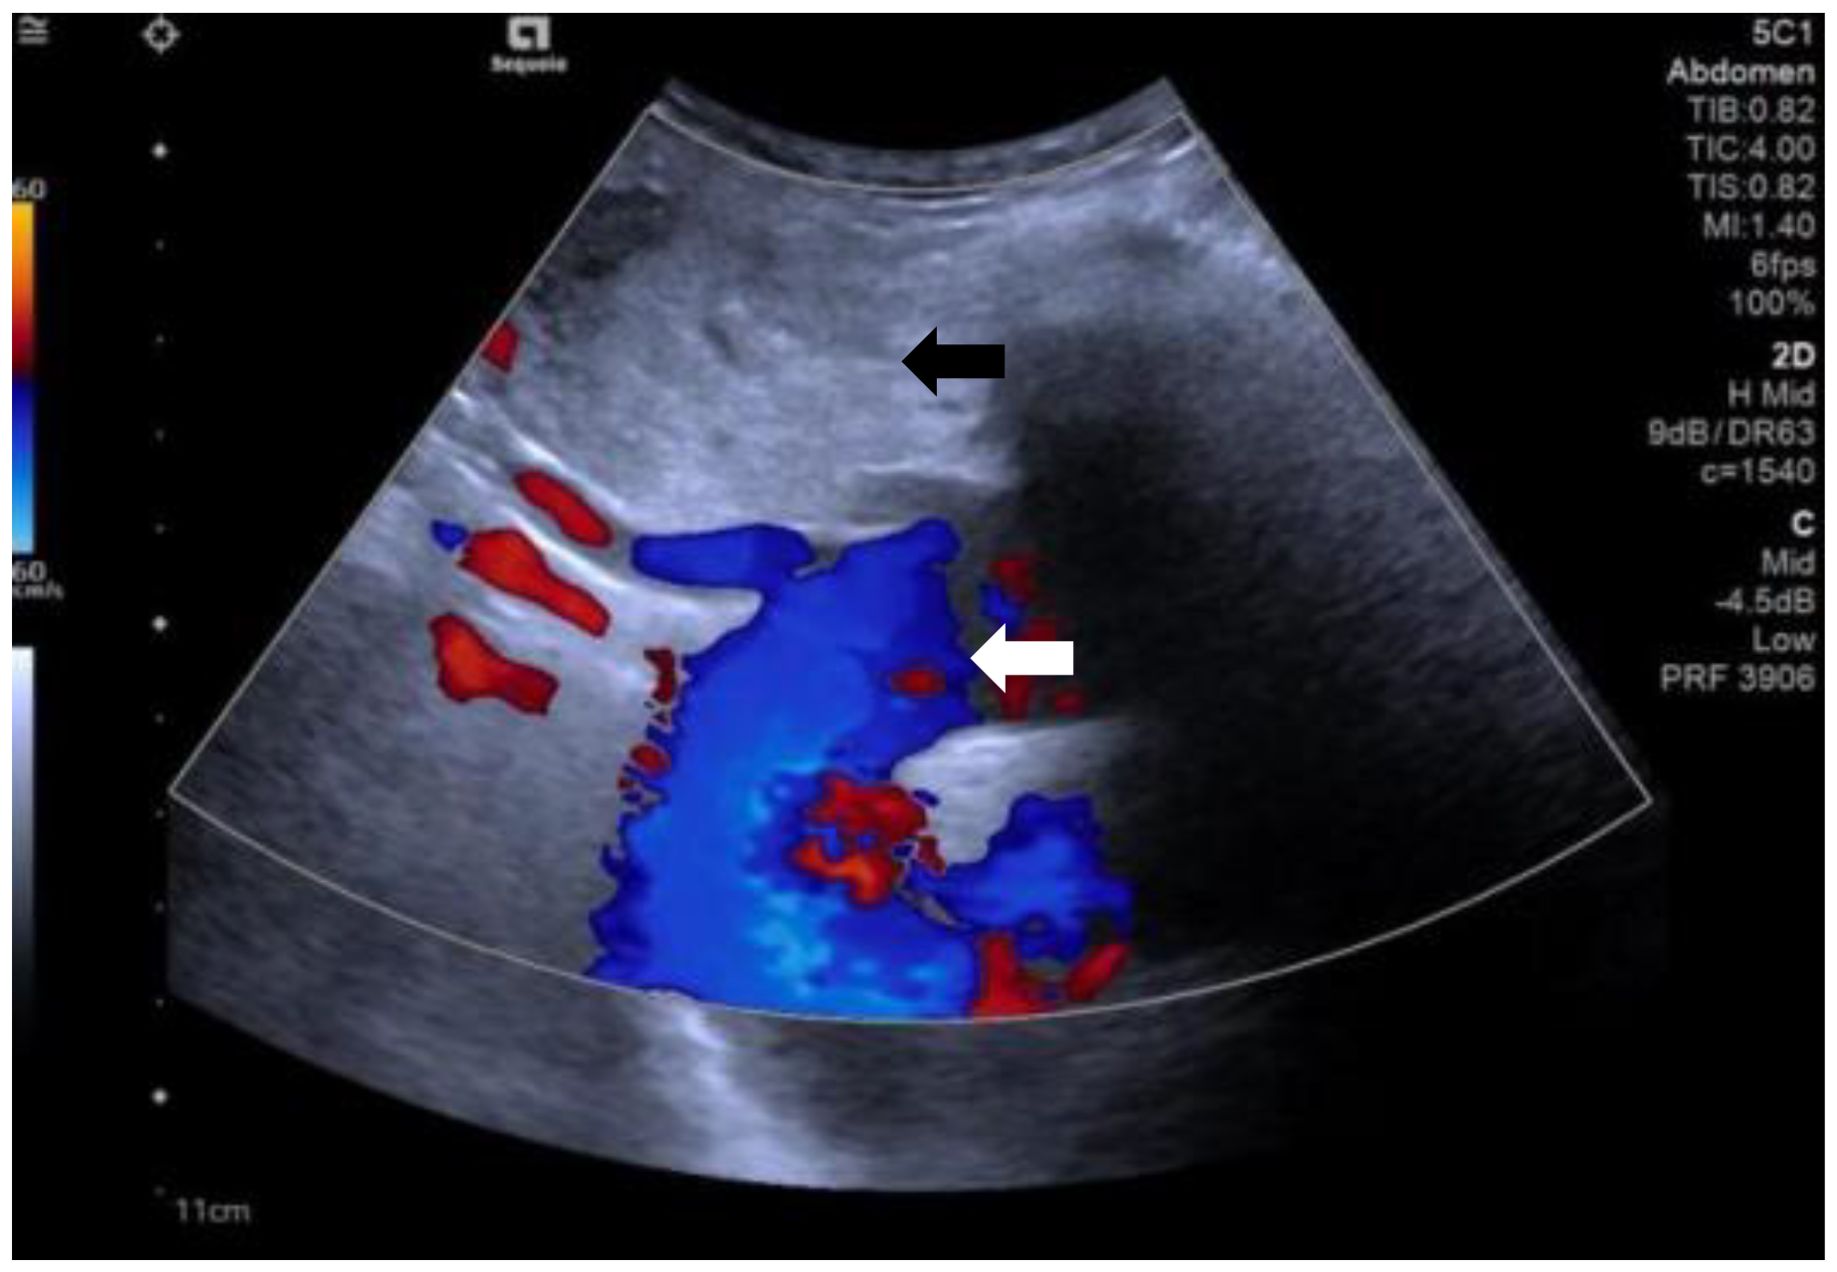

A 60-year-old female patient presented to our hospital with a history of thyroid nodules found for more than 20 years. Recently, she had developed airway compression and choking while drinking water. She had undergone a right thyroid lobectomy for benign thyroid nodules 5 years ago. After admission, CT examination showed a significant enlargement of the left thyroid lobe, with a mixed-density mass measuring approximately 4.6×4.2×4.5 cm. The lesion displaced the trachea to the right and extended into the anterior superior mediastinum, compressing the aortic arch, right subclavian artery, and left common carotid artery. Notably, the patient had a congenital vascular anomaly, with the aortic arch giving rise to the cephalic trunk, right subclavian artery, and right common carotid artery from left to right (Figure 1). The ultrasound examination showed that the left lobe of the thyroid gland was morphologically abnormal and significantly enlarged, with an inhomogeneous hypoechoic mass measuring about 4.9x4.5x4.7 cm, which was projecting into the upper mediastinum and compressing the aortic arch and its branch vessels (Figure 2). Laboratory tests for thyroid function and parathyroid function were normal, and a preliminary diagnosis of substernal goiter was made.

Figure 2. The ultrasound shows substernal goiter (black arrow) compressing the aortic arch and its branch vessels. (white arrow).